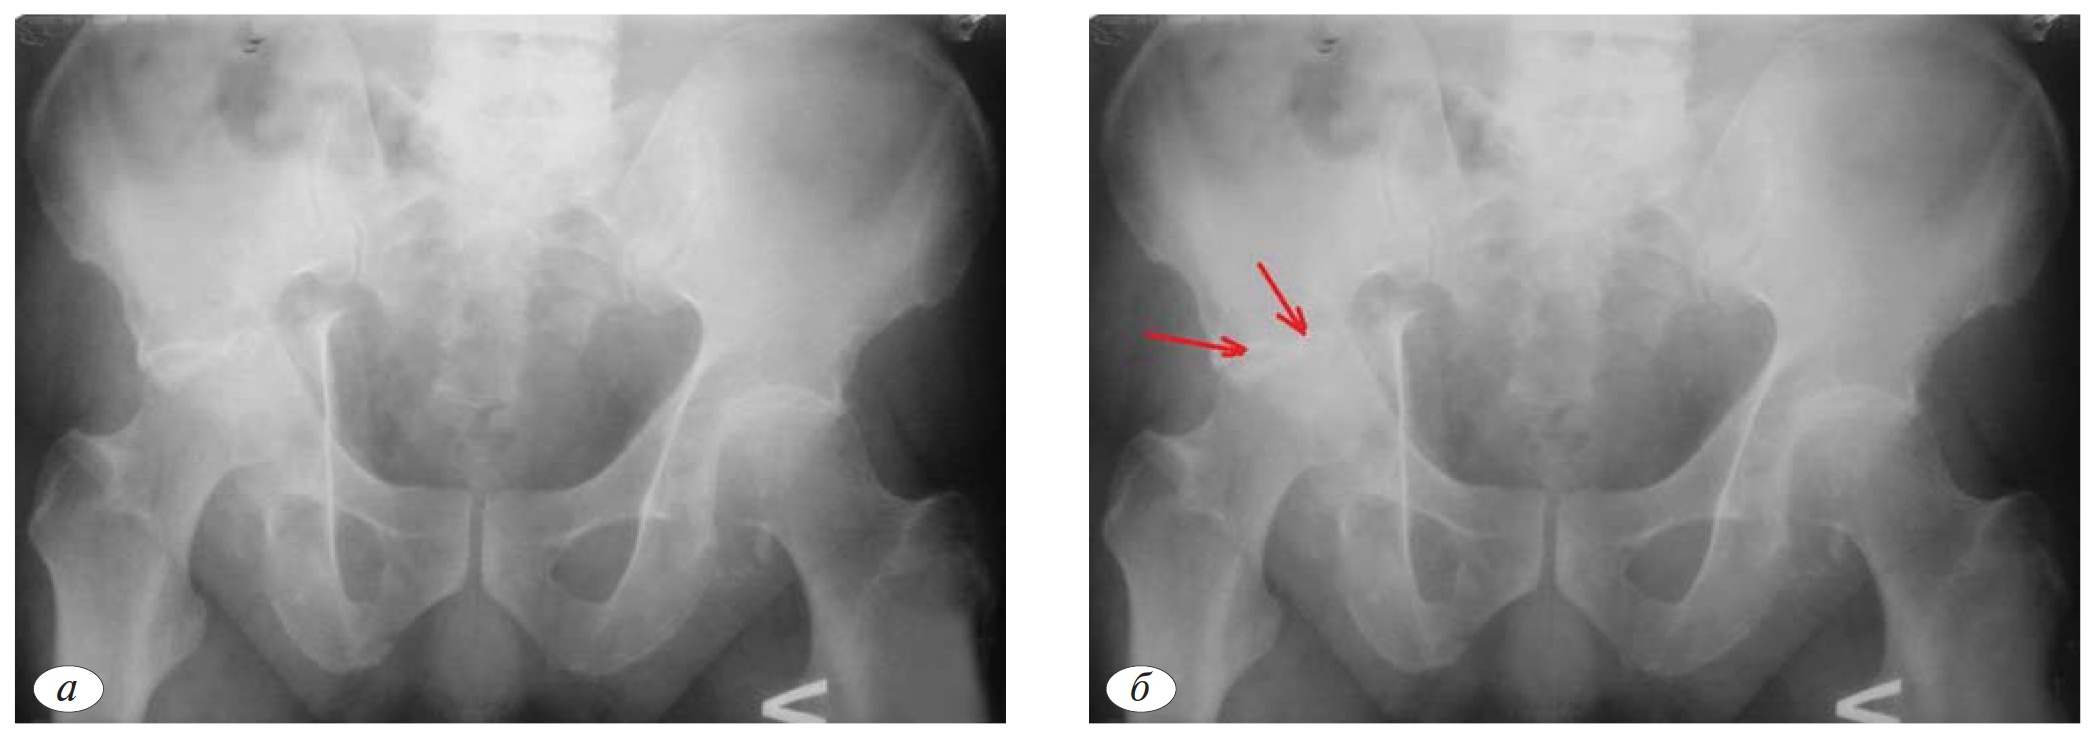

На обзорной рентгенограмме таза (рис. 1, а) определяется сочетание нарушений контуров трех линий (подвздошно-гребешковая, подвздошно-седалищная, контуры запирательного отверстия), характерное только для 3 типов ассоциированных переломов: Т-образного перелома, перелома передней колонны, ассоциированного с задним полупоперечным переломом, двухколонного перелома. Таким образом, на первом этапе из 10 возможных типов переломов, мы можем исключить 7 типов (рис. 1, а).

Целостность крыла подвздошной кости, как уже было отмечено ранее, позволяет исключить типы переломов, при которых наблюдается отдельный фрагмент передней колонны (перелом передней колонны, ассоциированный с задним полупоперечным переломом, двухколонный перелом). Таким образом, методом исключения диагностирован Т-образный перелом (рис. 1, в).

Рис. 1.а — обзорная рентгенография таза при поступлении; б — первый этап определения атипичного Т-образного перелома ассоциированного с переломом задней стенки; в — второй этап определения атипичного Т-образного перелома ассоциированного с переломом задней стенки; в — окончательное определение атипичного Т-образного перелома ассоциированного с переломом задней стенки; г, д, е, ж, з — детализация атипичного Т-образного перелома ассоциированного с переломом задней стенки с помощью прицельных рентгенограмм в подвздошной и запирательной проекциях и компьютерной томографии.

Однако при дальнейшем анализе обзорной рентгенограммы обращает на себя внимание отдельный фрагмент задней стенки. Соответственно в данном клиническом примере имеет место не Т-образный перелом, а атипичный Т-образный перелом, ассоциированный с переломом задней стенки (рис. 1, в).

Выполнение прицельных рентгенограмм и КТ позволяет подтвердить характер перелома. Как на рентгенограммах, так и на КТ отчетливо видна поперечно ориентированная линия перелома, проходящая через свод вертлужной впадины (транстектальный перелом), которая разделяет латеральные отделы тазового кольца на крыло и тело подвздошной кости и лобково-седалищный сегмент.

На прицельной рентгенограмме в запирательной проекции и КТ определяем отдельную плоскость излома, которая располагается в области задней стенки (рис. 1, д, з).

На рис. 1, ж видна вертикальная линия перелома, которая разделяет лобково-седалищный сегмент на передний и задний фрагмент (линия проходит через четырехстороннюю пластинку). Очень важно при планировании операции учитывать, что лобково-седалищный сегмент состоит из двух фрагментов.